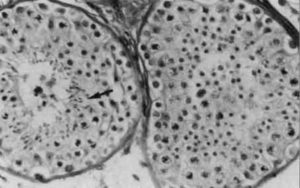

Тератозооспермия часто появляется из-за недостаточности яичек. Она проявляется дегенеративными изменениями зародышевого эпителия и существенным уменьшением количества вырабатываемой семенной жидкостью. Иногда даже гормональный анализ не может помочь в диагностике заболевания. В этом случае единственным способом для выявления истинной причины нарушений является тестикулярная биопсия.